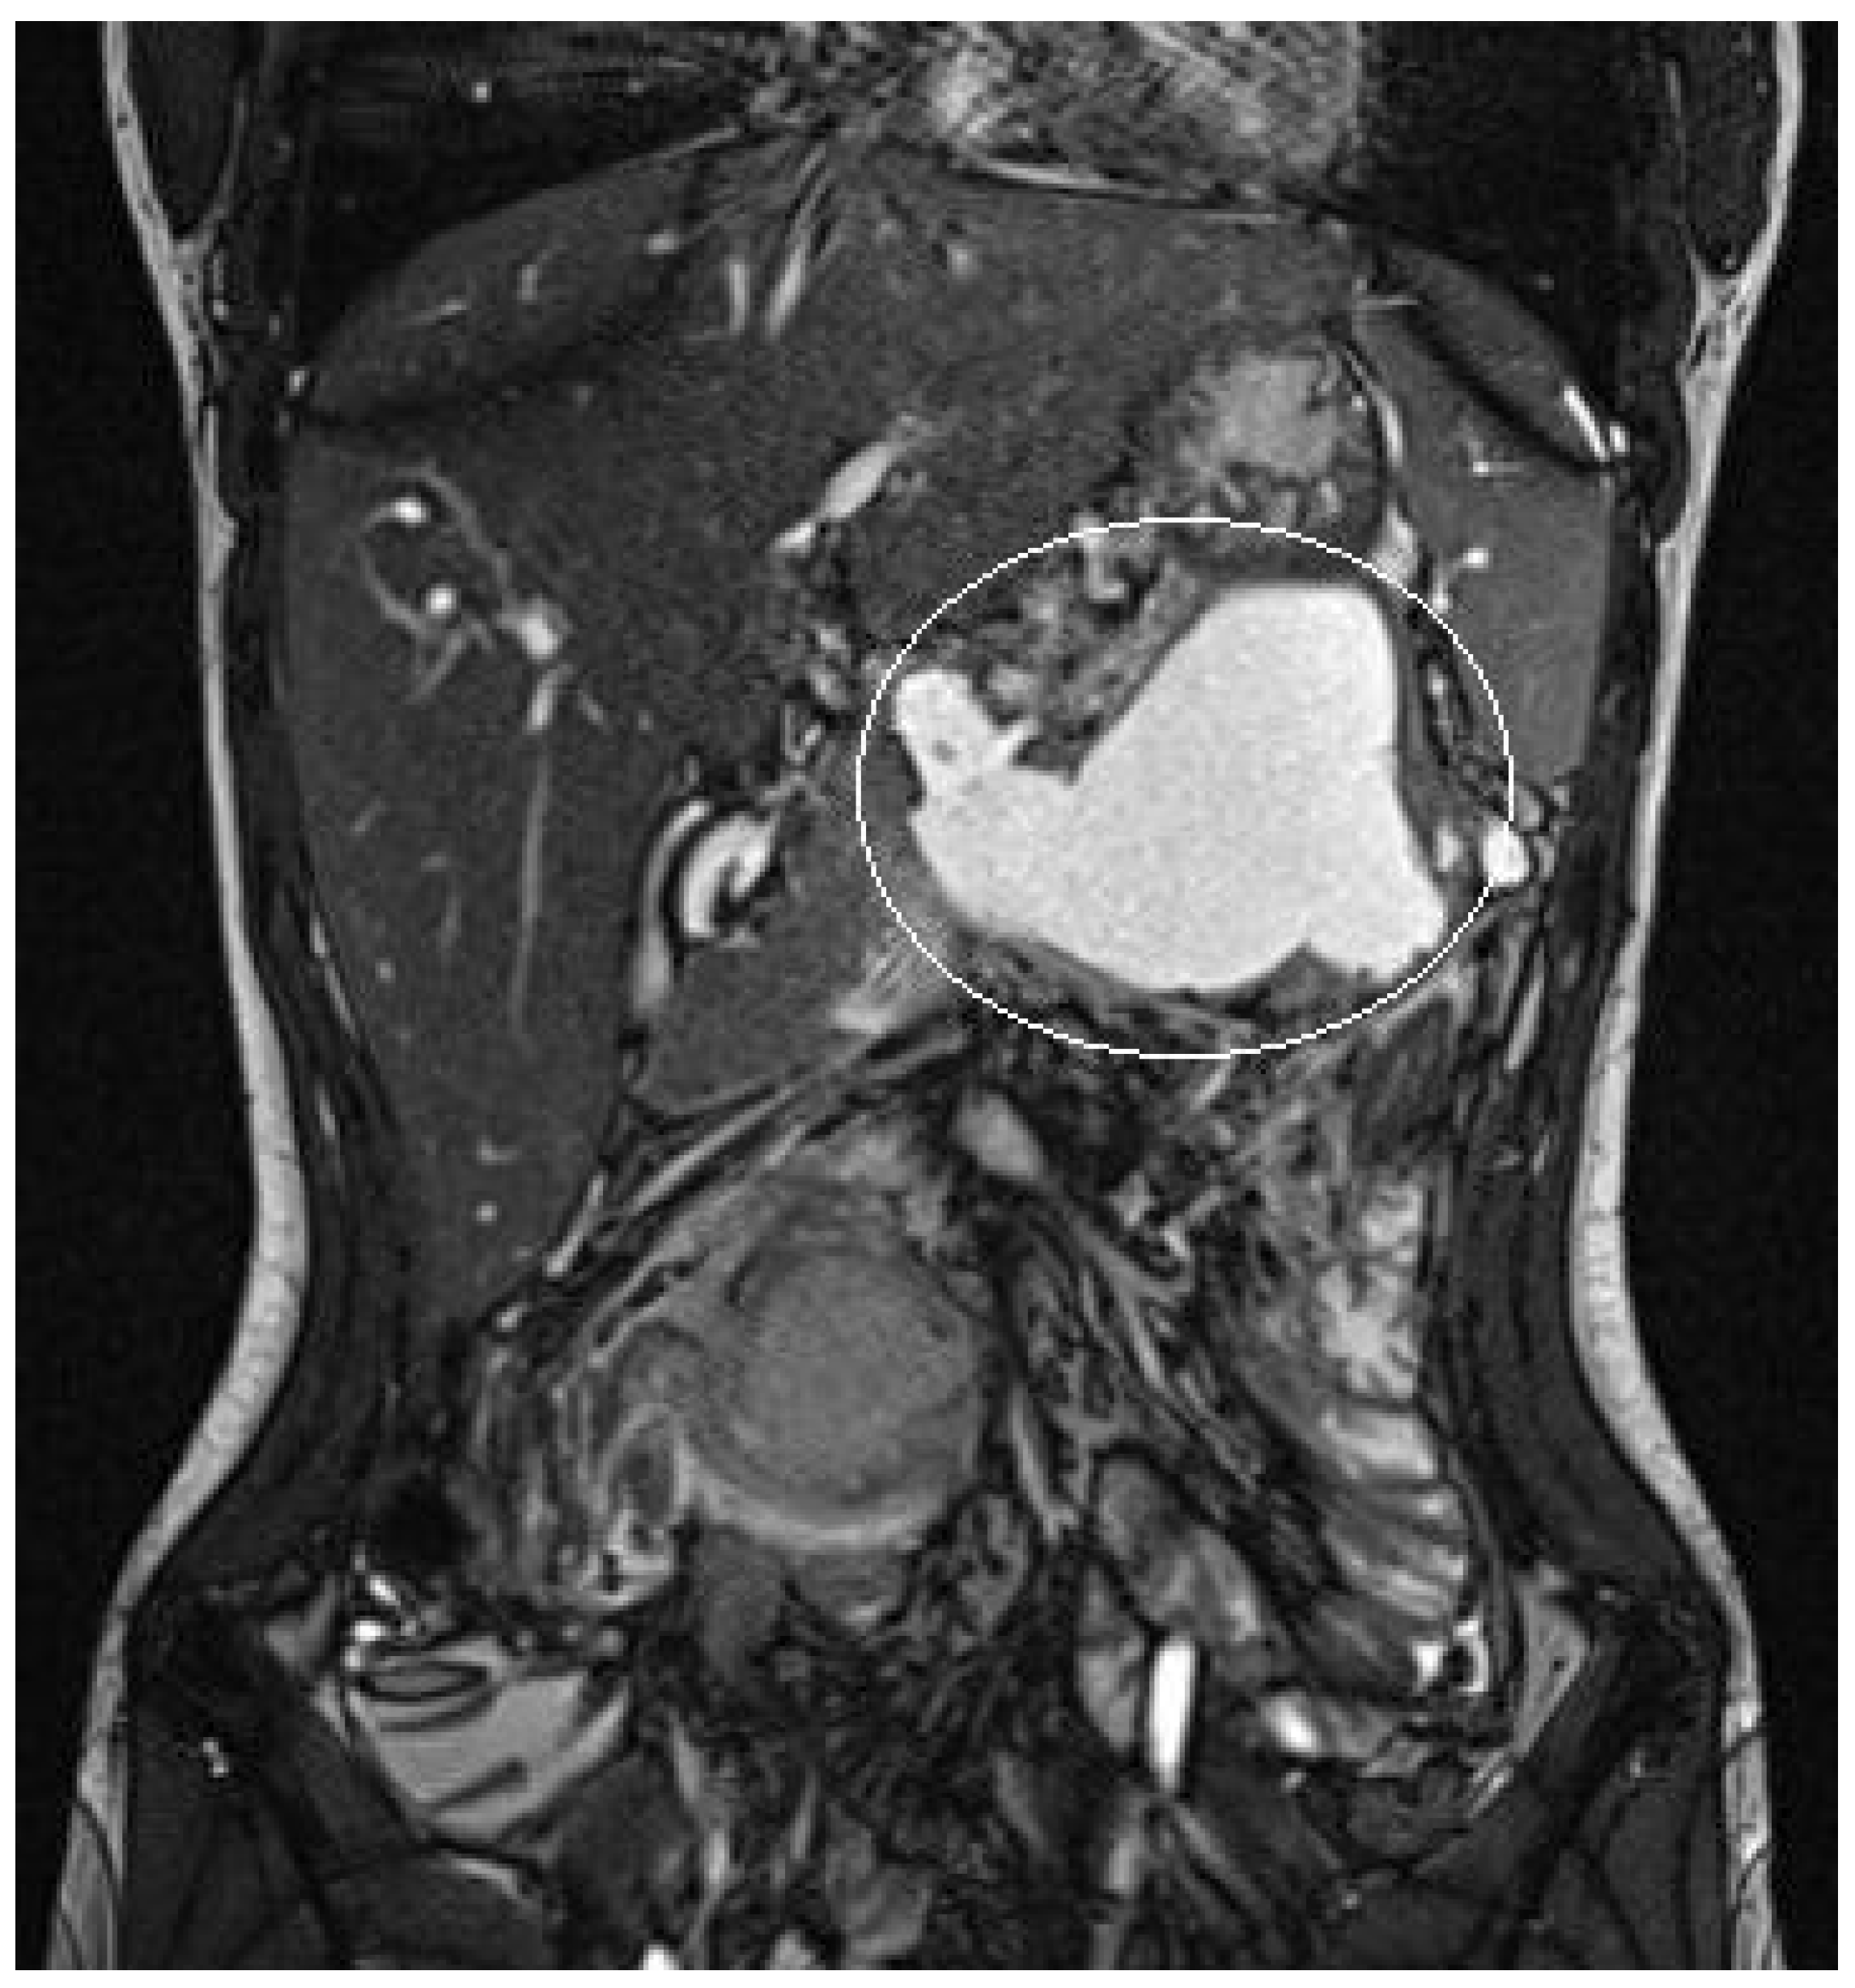

A 10-year boy affected by T-lymphoblastic lymphoma developed a WON after chemotherapy-induced necrotic-hemorrhagic pancreatitis, with fever, vomit and abdominal pain. Clinical conditions were also complicated by deep vein thrombosis involving the left femoral vein and inferior vena cava. Abdominal CT showed a large WON, with a major diameter more than 22 cm (Figure 5). Considering the worsening of clinical condition and the need to an early resume of the chemotherapy, he underwent a primary EUS-guided cystogastrostomy and EC-LAMS positioning; we did not perform necrosectomy. Post-operative course was uneventful. MRI performed 37 days after the procedure, showed a significant reduction of the WON (Figure 6); subsequent US images were performed for follow-up, until the WON was no more visible. Endoscopic removal of the device was performed 48 days after cystogastrostomy.

Figure 5.

Patient n°3 CT. Necrotic-hemorrhagic pancreatitis (body/tail origin) with voluminous walled-off necrosis developing in the left quadrant (hypochondrium/flank; relations to stomach, spleen, kidney, descending colon), extending craniocaudal about 22 cm.